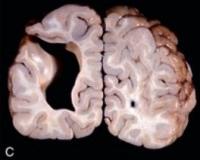

Размеры патологических полостей варьируются в широких пределах, в тяжелых случаях они занимают все полушарие. Изнутри новообразования имеют гладкую поверхность, покрытую эпендимальной оболочкой. Под микроскопом определяются участки гетеротопической коры головного мозга. Порэнцефальные кисты могут быть заполнены ликвором или кистозной жидкостью, которая имеет желтый цвет и содержит много белковых включений.